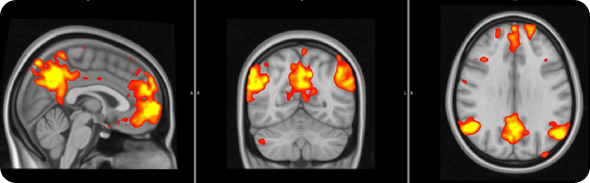

Fibro brain 1 - resized

In order to address this question, we used a brain imaging technique called ‘functional Magnetic Resonance Imaging’, which allows us to examine how brain activity changes in association with certain states or tasks.

In this study brain activity was investigated when the participants received painful stimuli, as well as when they received visual cues informing the subjects of impending pain onset (pain anticipation) and pain offset (relief anticipation).